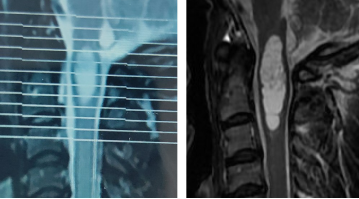

图2 张先生2016年(左)和2020年(右)核磁图像,提示肿瘤明显增大

命运的残忍像极了躲在门后的刽子手,恐惧袭来,随时要带走一切美好。今年三月份张先生体检复查,发现脊髓肿瘤长大了,再不做手术的话,恐怕将来手术成功的可能越来越渺茫。经过四处求医问诊,张先生一家慕名找到了国内脊髓肿瘤外科专家——北京清华长庚医院神经外科主任王贵怀教授。

图3 张先生在我院复查的核磁,病变范围从延髓到颈3椎体上缘

据王贵怀主任介绍,张先生罹患的是一种脊髓髓内肿瘤,很多病人长时间都没有明确症状,有些人会有“颈椎病”类似的表现。从患者目前的影像检查和病史来判读,考虑是室管膜瘤,它是脊髓常见的髓内肿瘤,这种病药物无法治愈,只能通过手术治疗,如果能够做到全切,术中对正常神经充分保护的话,病人将开启下一段正常的人生。但是肿瘤位置特殊,长在延髓到颈3椎体水平的脊髓内,手术需要切开脊髓进行,稍有不慎就会导致病人瘫痪,甚至呼吸心跳骤停,手术风险和难度极大。